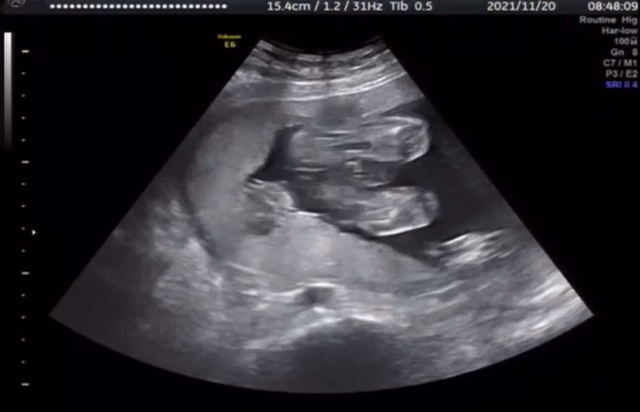

21w3d ほぼ性別確定☆